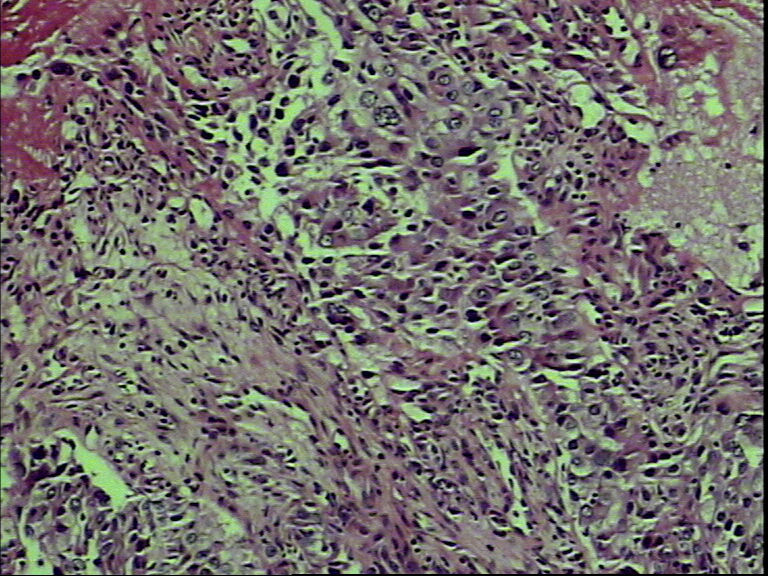

支气管活检,女性,65岁

• 支气管活检,女性,65岁图3

图3

鳞癌?腺癌?

鳞状细胞癌

组织太少,考虑鳞癌(建议再检)。

就本例而言基本肯定是鳞状细胞癌,退一步讲是腺癌的话,也不需再次活检了,排除小细胞癌了,不影响治疗方案了,只要其他情况还好的话,手术治疗是首选了。

图片质量太差 需排除腺鳞癌